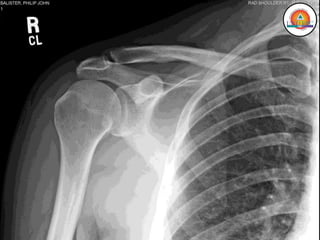

MIEMBRO SUPERIOR

• Cintura escapular (Escápula y Clavícula)

Huesos:

• Escápula

• Clavícula

• Húmero

• Radio

• Cúbito

• Carpo

• Metacarpo

• Falanges

Escápula

Clavícula

Húmero

Radio y Cúbito

Carpo, Metacarpo,

Falanges